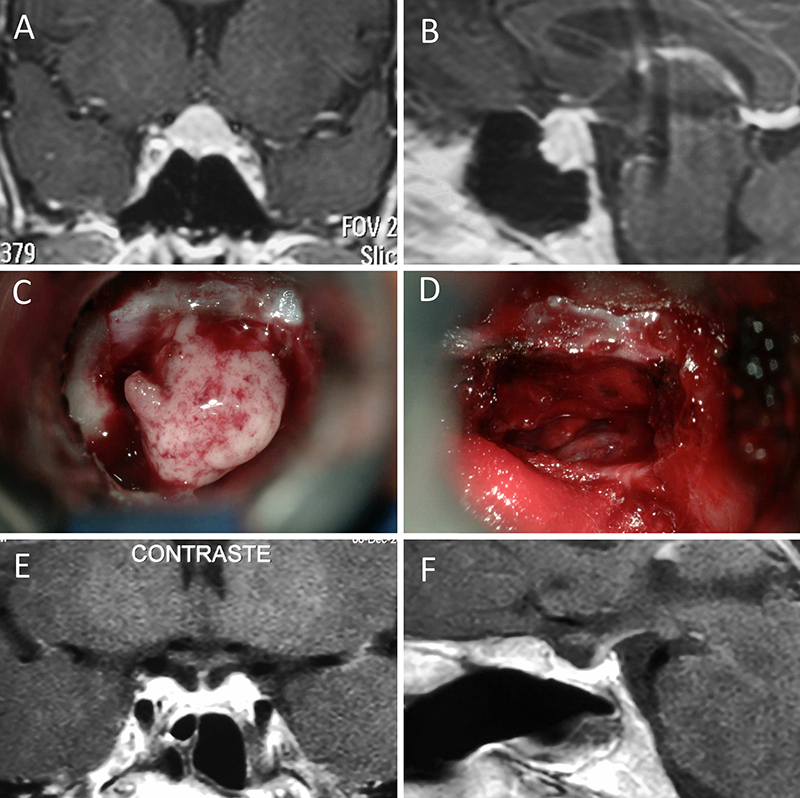

Figura 2: Macroadenoma no funcionante en mujer de 31 años. La paciente presentó en el preoperatorio déficit visual que mejoró tras la cirugía. A-B: RM preoperatoria; C-D: intraoperatorio; E-F: RM postoperatoria.

Figura 3: Macroadenoma no funcionante en un hombre de 64 años. El paciente presentó en el preoperatorio déficit visual que mejoró tras la cirugía. A-B: RM preoperatoria; C-D: intraoperatorio; E-F: RM postoperatoria.